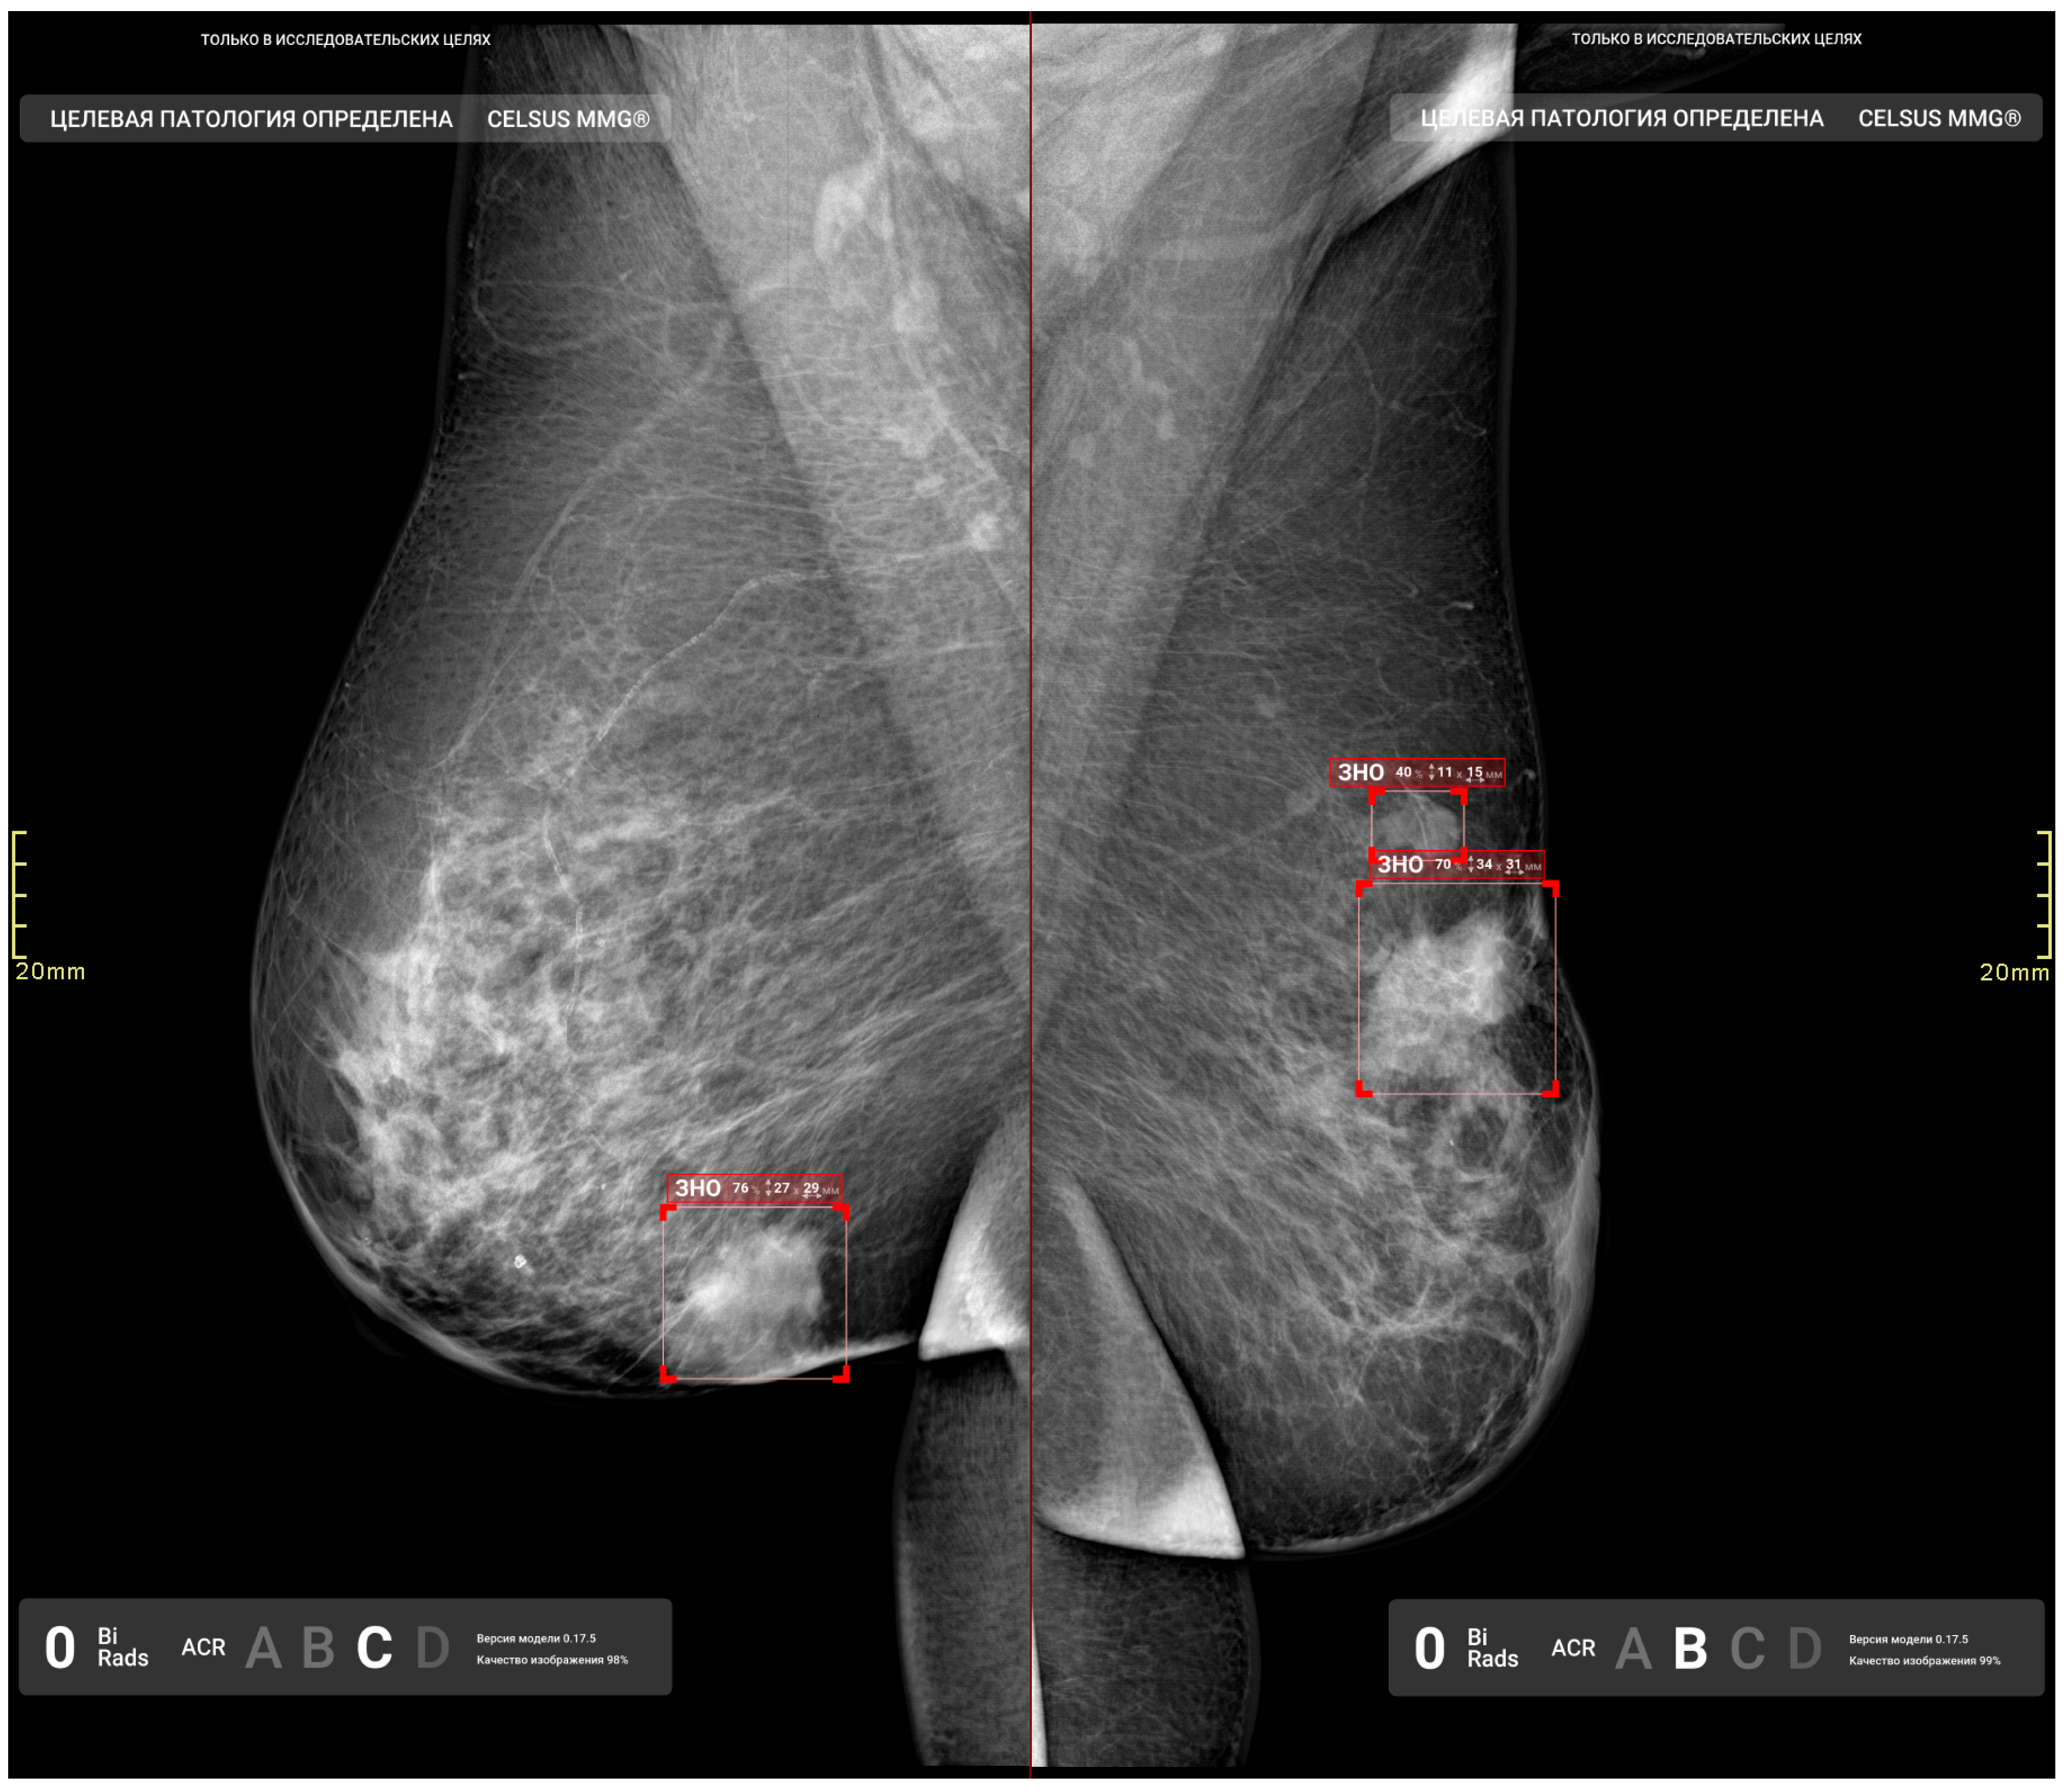

2.5.2. Functional Testing

| 1 | Detection, segmentation, and classification (benign/malignant) of masses | Graphical mask, text | DICOM, DICOM SR, Apache Kafka message |

| 2 | Detection, segmentation, and classification (benign/malignant) of calcifications | ||

| 3 | Detection and segmentation of enlarged lymph nodes | ||

| 4 | ACR category of breast density for each breast | Text | DICOM SR |

| 5 | Probability of breast cancer in the entire study | Number | Apache Kafka message |